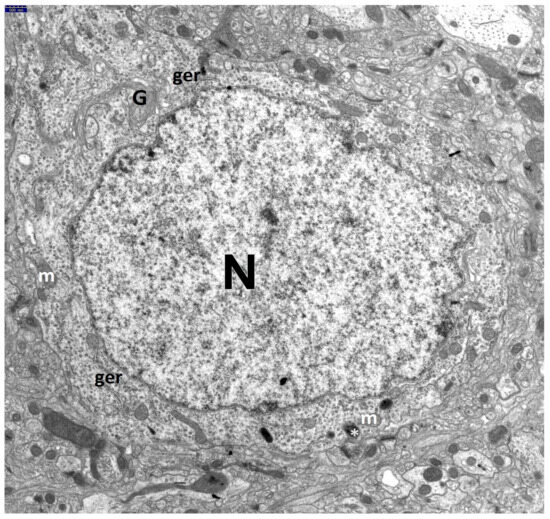

3. Results